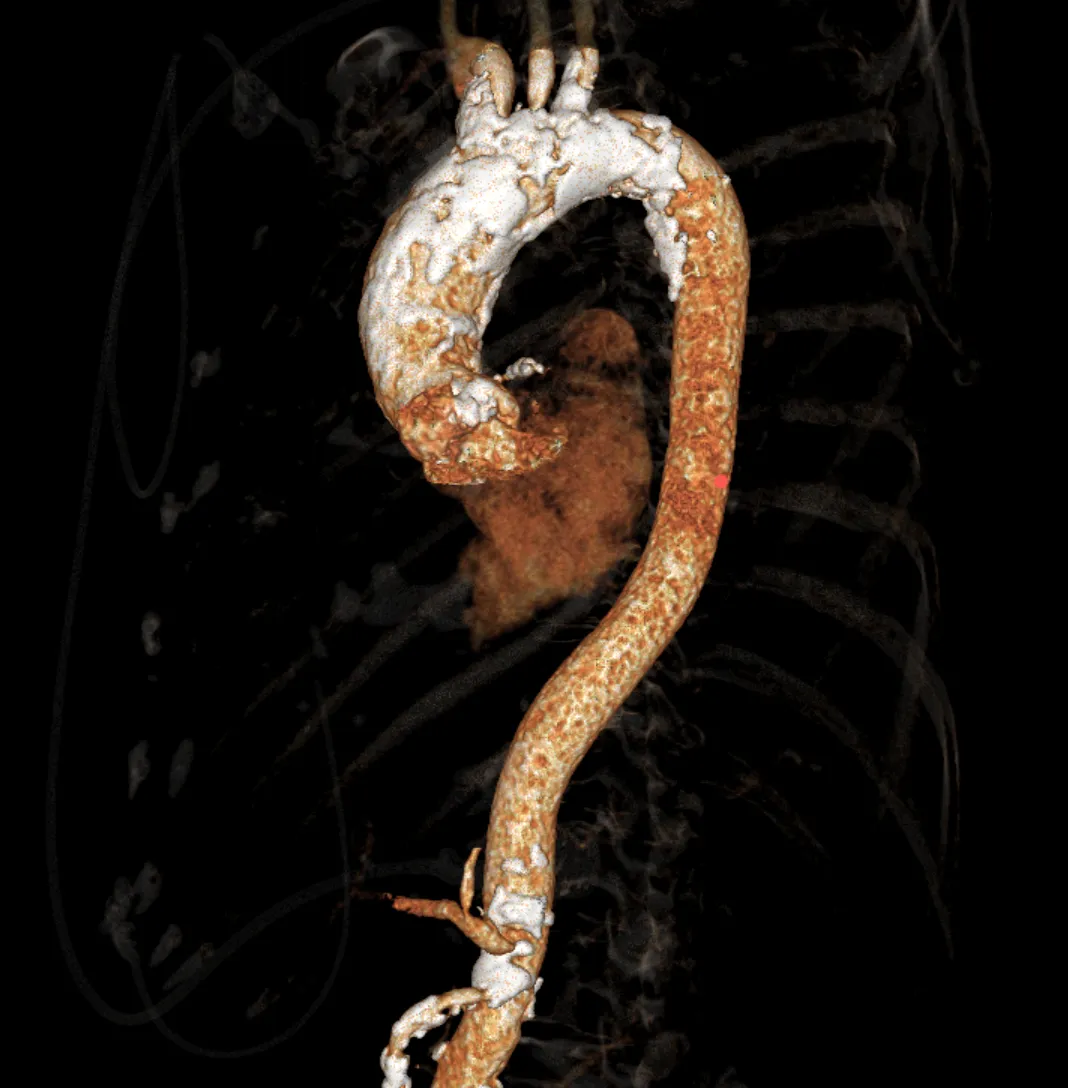

外周双侧入路无明显迂曲、直径可容纳20F大鞘通过,双侧中分叉,穿刺需注意。主动脉弓角弓距可,髂总动脉及分支多处钙化,瓷化升主动脉,钙化由升主动脉蔓延至主动脉弓侧壁及弓顶弓底部,有一定卒中和夹层风险。

过弓示意图